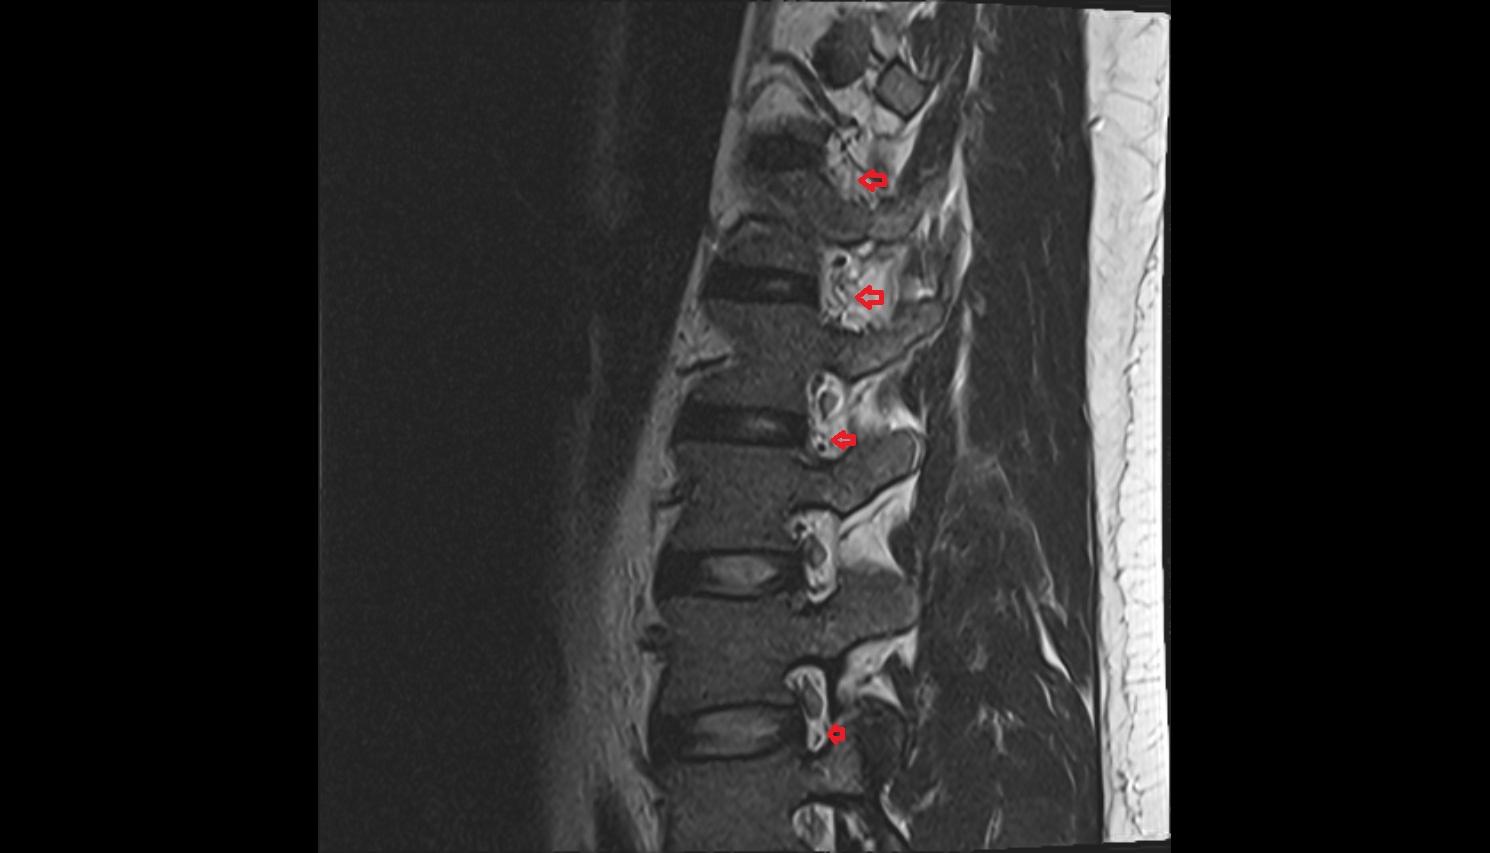

- Facet joint of vertebra (Zygapophyseal joints)

- Intervertebral Disc

- L4–L5 Intervertebral Disc

- L3–L4 Intervertebral Disc

- L2–L3 Intervertebral Disc

- L1–L2 Intervertebral Disc